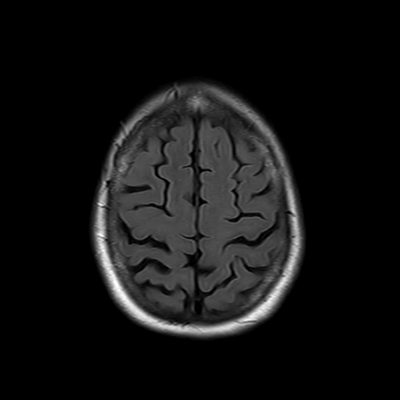

You also obtain an MRI of his brain once it's clinically safe to do so.

MRI brain (FLAIR)

You are now very concerned that he truly has an infectious meningoencephalitis.